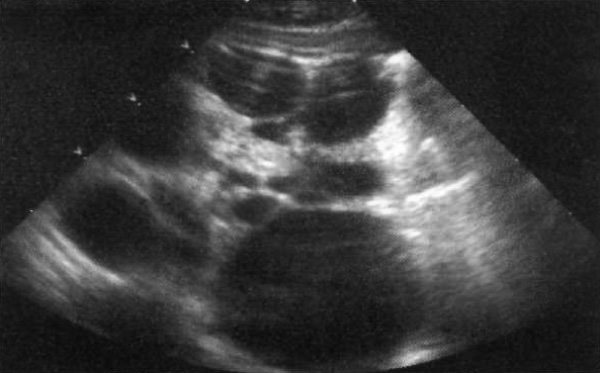

Характерной ультразвуковой картиной аутосомно-рецессивного поликистоза является двустороннее увеличение и повышение эхогенности почек без дифференцировки на мозговое и корковое вещество (фото 5).

Фото 5. Аутосомно-рецессивный поликистоз почек. А – продольное изображение правой почки. B – продольное изображение левой почки 9-летнего пациента. Стрелками обозначены множественные мелкие кисты; также отмечается общая повышенная эхогенность, плохая дифференцировка мозгового и коркового вещества